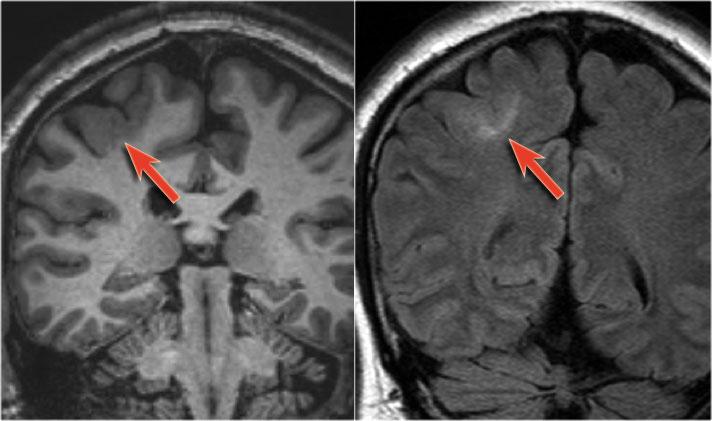

Một trường hợp loạn sản vỏ não khu trú khác.

Lưu ý hình ảnh thùy thái dương trái kém phát triển với dày vỏ não (mũi tên) và teo chất trắng.

Ảnh chuỗi xung T1W, T2W và FLAIR mặt phẳng axial của bệnh nhân nam 15 tuổi bị động kinh.

Lưu ý hình ảnh dày và tăng tín hiệu vỏ não hồi trán trên bên trái.

Ảnh FLAIR cũng cho thấy tăng tín hiệu ở chất trắng dưới vỏ.

Các dấu hiệu này điển hình cho loạn sản vỏ não khu trú.

Hình ảnh của bệnh nhân nam 27 tuổi bị động kinh thùy chẩm kháng trị.

Ảnh FLAIR mặt phẳng coronal và T2W mặt phẳng axial cho thấy dày vỏ não tăng tín hiệu T2 và tăng tín hiệu ở vỏ não và vùng dưới vỏ.

Lưu ý vùng tăng tín hiệu dưới vỏ kéo dài đến não thất bên phải, biểu hiện dấu hiệu xuyên vỏ (mũi tên xanh).

Dấu hiệu xuyên vỏ (transmantle sign) ghi nhận ở một bệnh nhân khác bị loạn sản vỏ não khu trú.